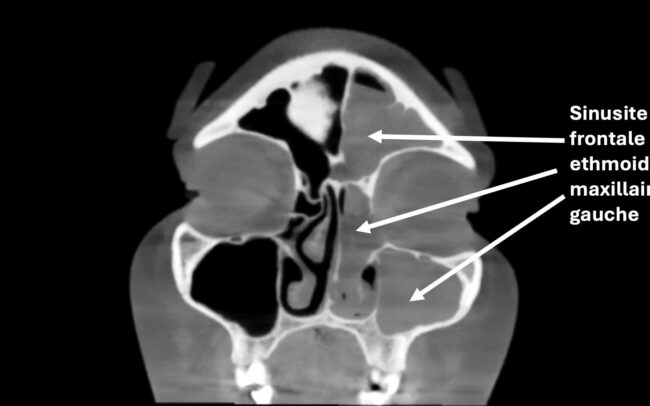

Sinusite chronique

La sinusite chronique est une inflammation persistante des sinus, qui dure plus de 12 semaines.

Symptômes : On retrouve un nez bouché, des douleurs faciales, un écoulement nasal purulent ou clair, et/ou une perte partielle ou totale de l’odorat.

Traitement : Il repose sur les lavages de nez avec du sérum physiologique, les sprays à base de cortisone, les antibiotiques en cas de surinfection, et les antihistaminiques si une composante allergique est présente. Un traitement antibiotique au long terme (3 mois) peut être proposé dans certains cas. Si les symptômes persistent malgré le traitement médical bien mené, une chirurgie endonasale (par les narines, sans cicatrice visible) peut être proposée